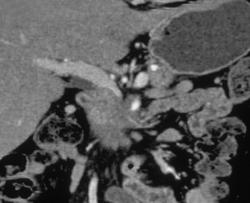

Pancreatic Cancer Encases the PV/SMV